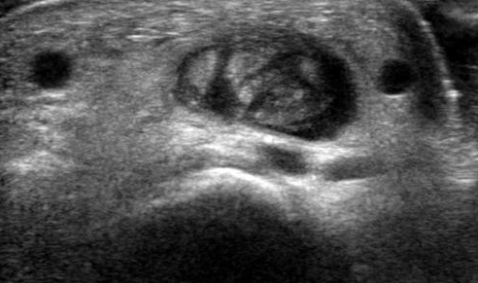

Tenosynovite de la jeune maman (de Quervain)

- Ténosynovite du premier compartiment

- Mères qui portent leur enfant ++

- Inflammation des tendons au niveau de la styloide radiale

tendon extenseur teno téno bebe enfant bébé berce berçant